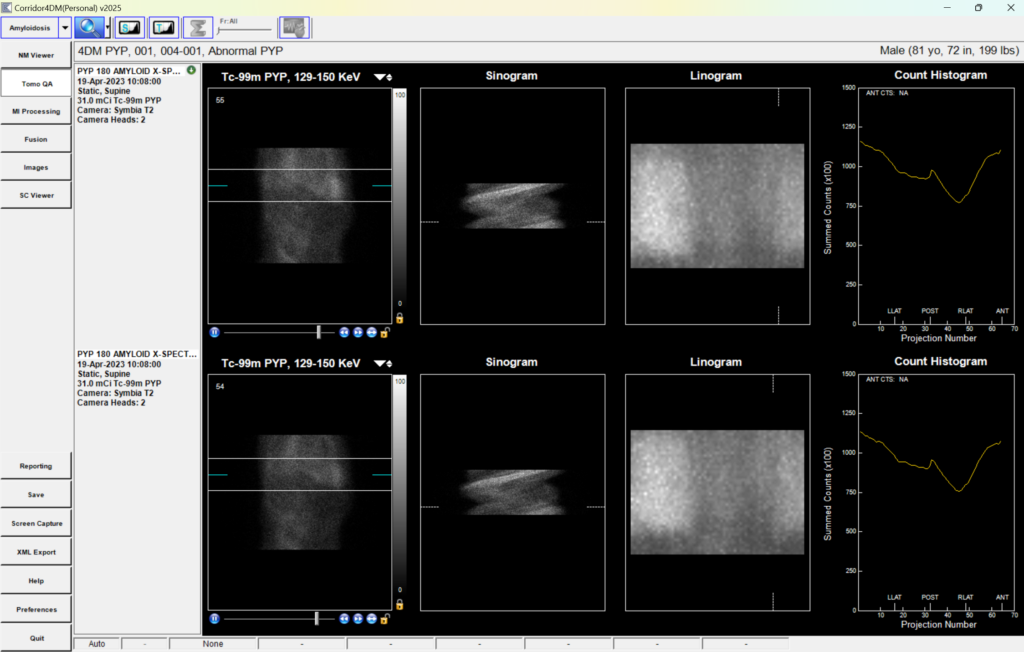

- Amyloidosis Workflow

Automated Amyloid Report Templates

- Follows ASNC, IAC & ACR reporting guidelines

- Decreases report turnaround times with less manual data entry

Supports Amyloid Radiotracers

- Evuzamitide

- 99mTC-DPD